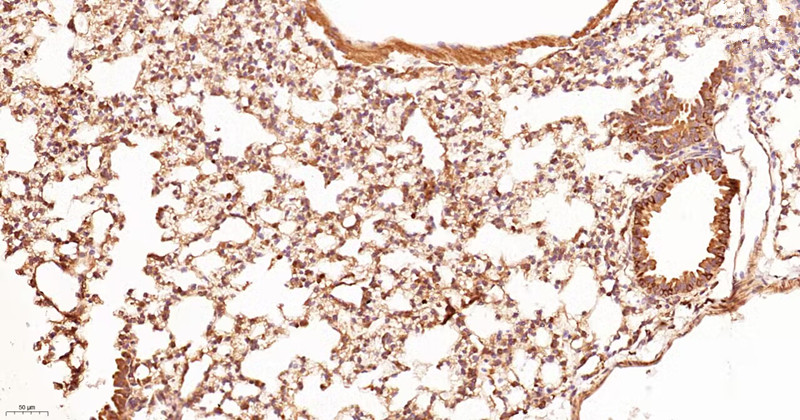

Immunohistochemical analysis of paraffin-embedded mouse lung, using CD11b Antibody.